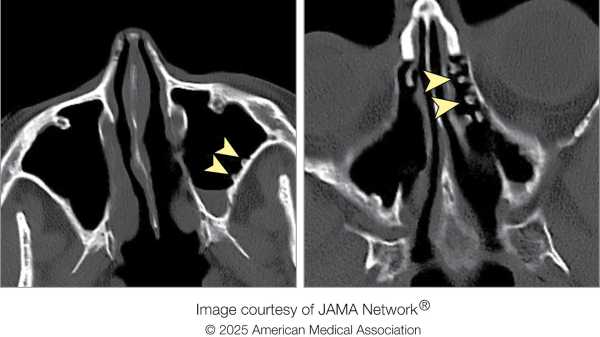

У лікарні рентгенівський знімок верхньої частини хребта чоловіка не виявив жодних відхилень. Однак посилення болю в хребті та скутість шиї спонукали одного з лікарів призначити комп'ютерну томографію (КТ) тієї ж ділянки. На КТ лікарі помітили «клиноподібний, гіперщільний об'єкт», – написали вони у звіті про випадок. Об'єкт проник у задню частину горла чоловіка та увійшов у його спинномозковий канал. Він застряг там, пробивши великий потиличний отвір – великий отвір біля основи черепа, через який проходить спинний мозок.

Діагноз: Лікарі негайно провели чоловікові операцію з видалення прониклого предмета. Вони ввели загальний наркоз, і хірург використав ретрактори — інструменти, що утримують рани відкритими, — щоб оголити предмет, який виявився зламаним кінчиком риб’ячого дзьоба.

Лікування: Гострий фрагмент дзьоба так міцно застряг у черепі чоловіка, що хірургу довелося зробити додатковий розріз над верхнім хребцем чоловіка, щоб видалити його, витягнувши вздовж шляху введення. Його довжина становила близько 3,5 сантиметрів (1,4 дюйма).

Згідно зі звітом, випадок цього чоловіка є першим зареєстрованим випадком травми великого потиличного отвору, а також першою травмою, спричиненою рибодзьобом.